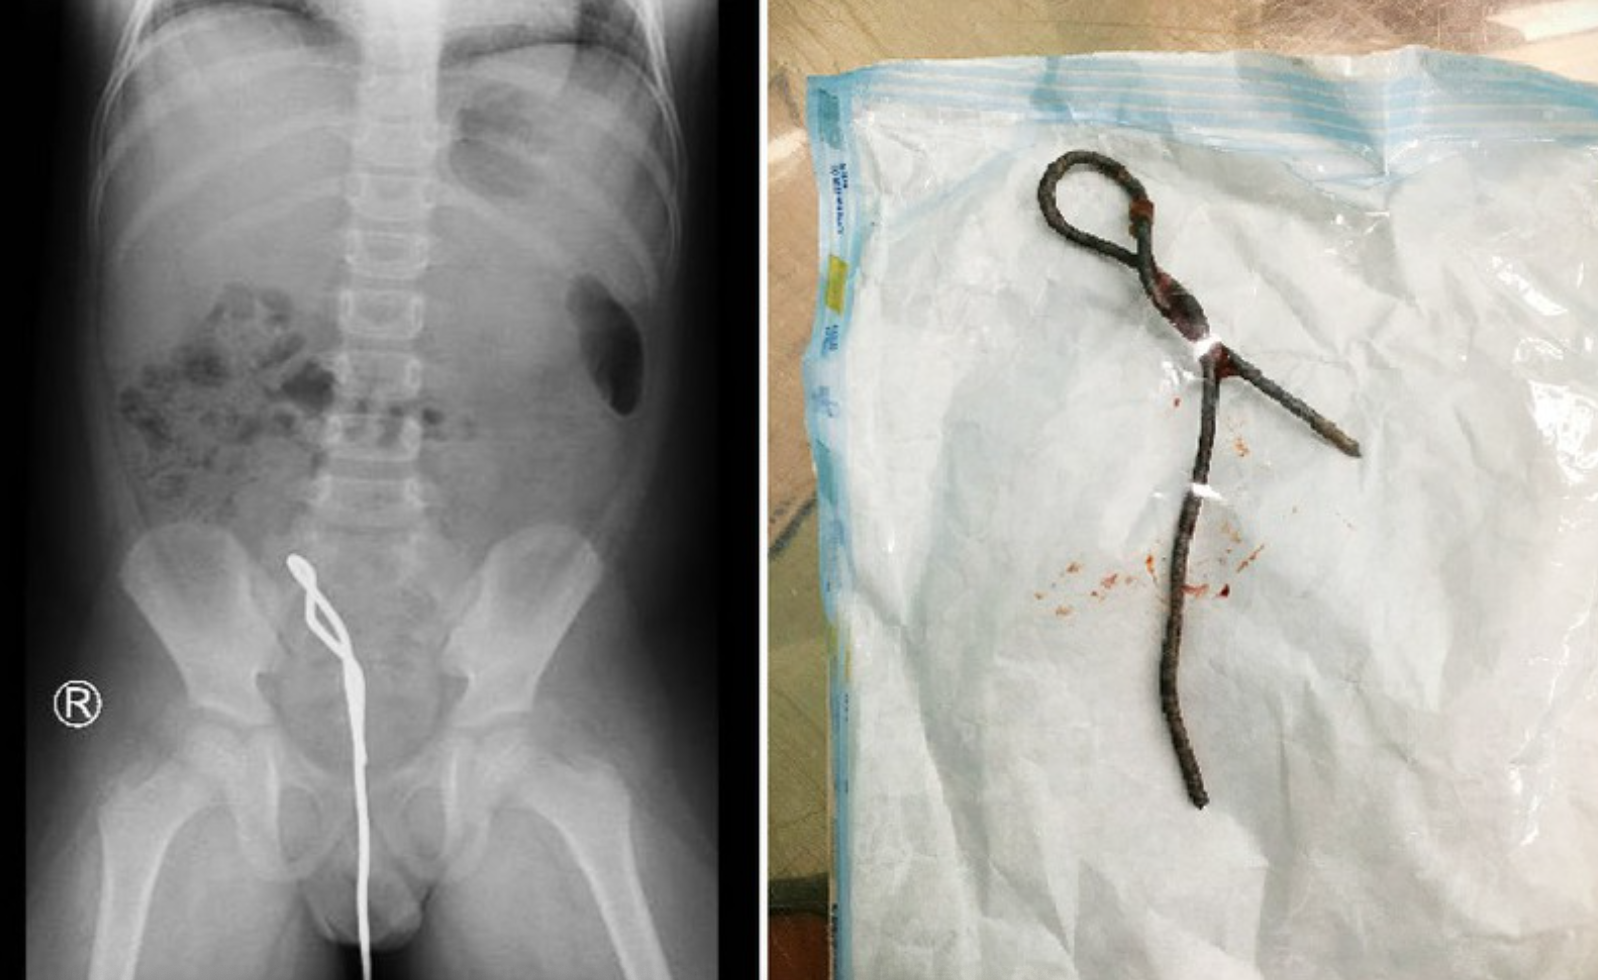

5. Học theo phim, bé trai nhét thanh sắt thông cống dài nửa mét vào hậu môn

Hình ảnh cây thông cống trong cơ thể bé trai và khi được lấy ra. Ảnh: BVCC